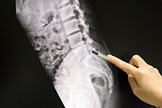

Lower Back Injury Diagnosis

Lower back injuries are often put through a gamut of tests because spinal injuries can cause life-altering sequelae such as paralysis, paresis, and death. Imaging and physical exam form the cornerstone of diagnosing these injuries.

Imaging

Imaging is not done for sciatica. For fighters, it’s important to still get plain films of the lumbosacral spine. The doctors should assess fractures, disc rupture, herniation, or spondylolisthesis. A non-contrast CT scan is performed if plains films don’t reveal any findings. If the fighter continues to experience pain for more than 6 to 8 weeks and does not respond to treatment, an MRI is done. For all neurologic deficits, an MRI must be done to rule out any spinal pathology.

The gold standard is an urgent MRI imaging with sagittal and axial sequences. Early MRI is needed to proceed with surgery as cauda equina syndrome can be fatal. Neurosurgical or orthopedic consultation must follow. Ideally, an MRI must be done within an hour from the presentation. A CT myelogram is an option for those with metal implants and cannot do an MRI. A bladder scan is also done to check for post-void residual volume. This is to evaluate any urinary retention.